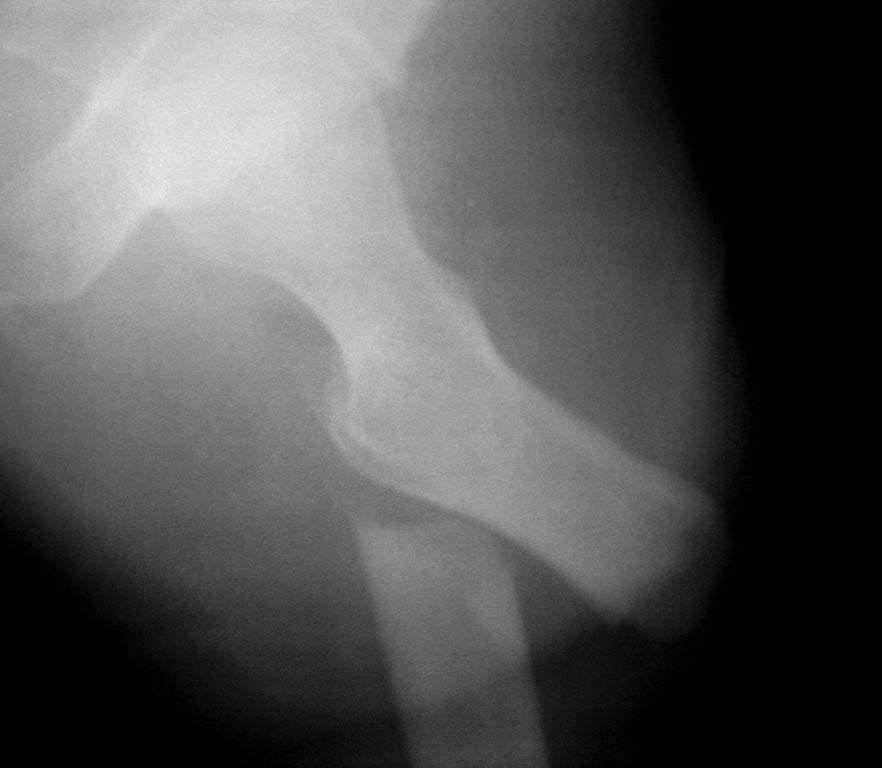

Нужен совет. Открытый перелом в\3 диафиза с оскольчатым переломом дистального метаэпифиза бедра. Закрытый оскольчатый внутрисуставной перелом проксимального отдела большеберцовой кости той же конечности.

При поступлении ПХО ран, скелетное вытяжение. Рана зажила первичным натяжением. Осложнилось правосторонней пневмонией. Предстоит выбрать тактику оперативного лечения и камими имплатнатами.